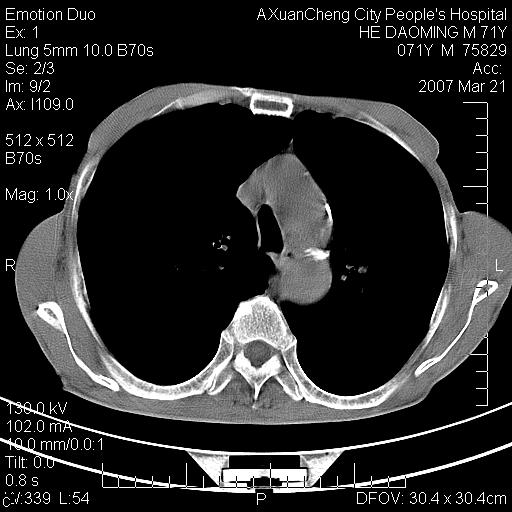

标题: CT7269:[原创] 咳嗽,咳痰,大家讨论右肺病变的部位

考虑:慢性支气管炎合并全小型肺气肿、肺大泡、间质纤维化、感染,右斜裂积液. 冠状动脉硬化(冠心病)

1.慢支肺气肿 肺心病 肺大泡;2.叶间裂积液,前胸膜粘连